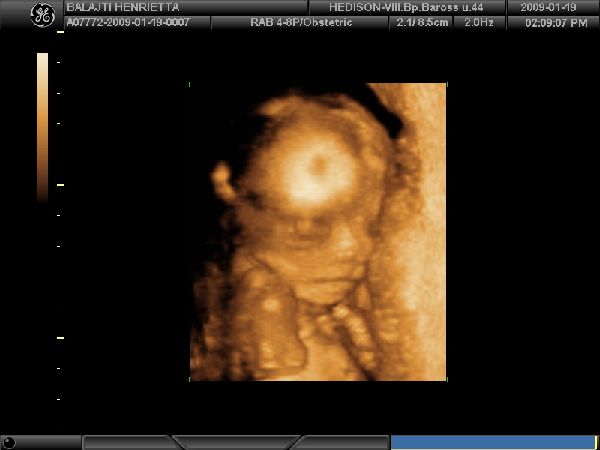

Egy kis mosoly

Egy kis mosoly  Hammm Bekapom

Hammm Bekapom  A kis Hercegnő!!!

A kis Hercegnő!!!

Kis Gyönyörűség

Kis Gyönyörűség  És Apája orra az én orrom

És Apája orra az én orrom